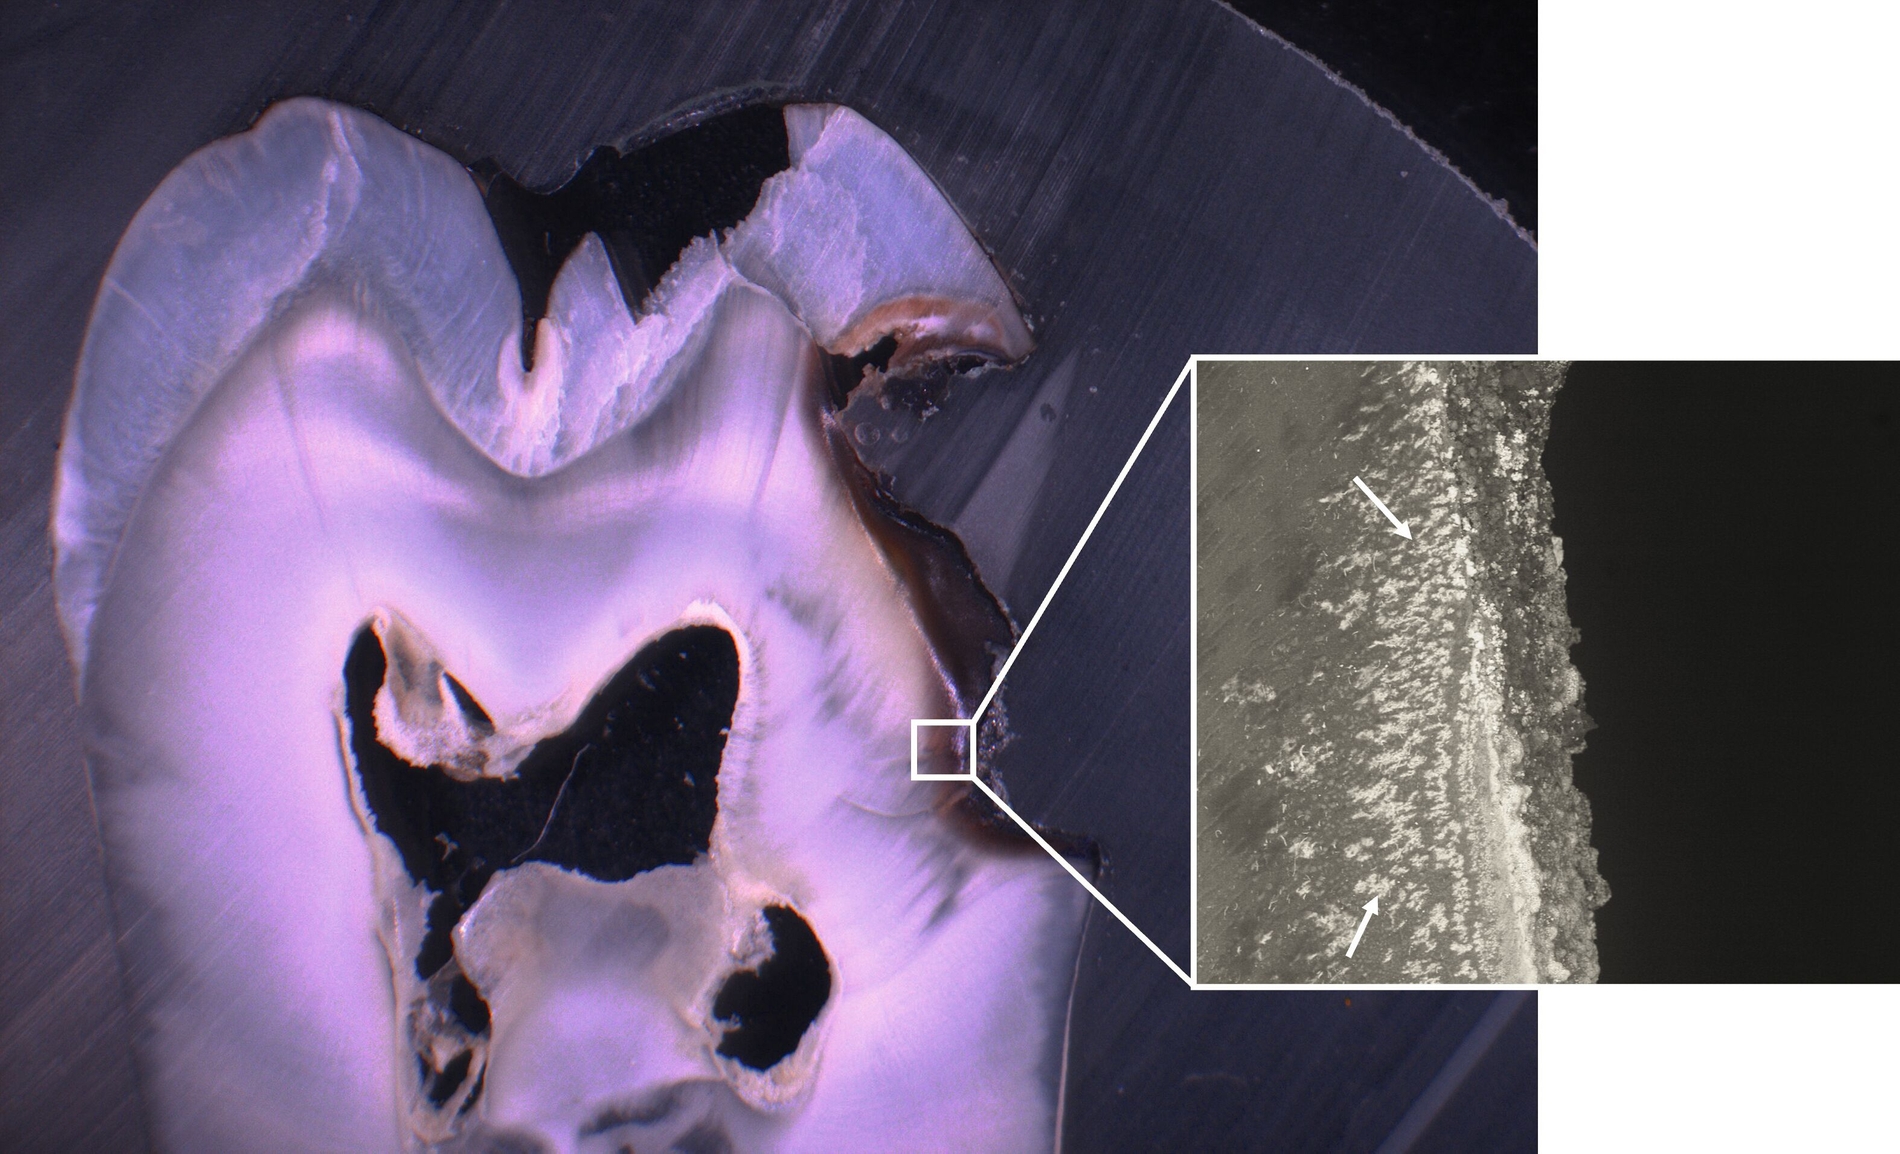

SDF ist besonders wirksam bei der Behandlung von Kariesläsionen (Abbildung 1). Bei der Anwendung auf kariösem Zahnhartgewebe dringen die Silberionen in die bakteriellen Zellwände ein, stören die bakterielle DNA-Synthese und den Stoffwechsel, und führen so zum Zelltod. Zusätzlich stabilisieren die Silberionen die kariösen Läsionen, indem sie die Dentinkanälchen blockieren (Abbildung 2) [Crystal, and Niederman, 2019].